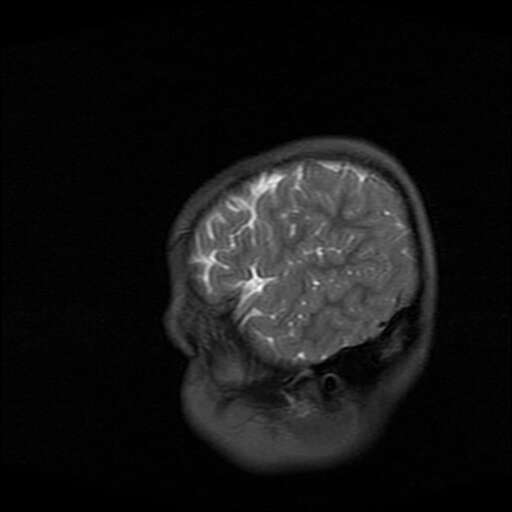

女,7岁,三岁才说话、走路。现智力尚可,走路不稳。临床怀疑大脑发育不全。

脑折质变薄,双侧侧脑室稍扩张,支持考虑脑折质发育不良

考虑胼胝体发育不全,髓鞘形成不良。

支持考虑胼胝体发育不全,髓鞘形成不良。

侧脑室周围白质数量减少,侧脑室不对称性扩大,左侧侧脑室后角呈方形改变,脑沟加深,结合临床考虑脑室周围白质软化症(pvl)。期待结果!